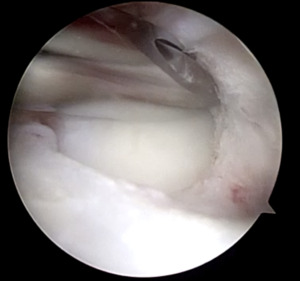

At the time of surgery, diagnostic arthroscopy revealed intact cartilage without any defects or abnormal wear. There was no evidence of a ligamentous injury. The medial meniscus was found to be intact (Figure 4).

The ACL and PCL were intact. The lateral compartment revealed a lateral meniscus tear with the tissue displaced centrally into the notch, impinging on the ACL (Figure 5).